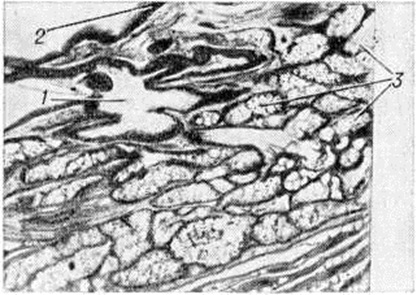

Рис. 2.

Рентгенограмма грудной клетки в прямой (1) и правой косой (2) проекциях больной с дермоидной кистой средостения (указана стрелкой). Пищевод, заполненный бариевой взвесью, отдавлен опухолью к позвоночнику (указан двумя стрелками).

Рентгенологическое исследование (рентгеноскопия, рентгенография, томография и другие специальные методики) представляет надёжный способ выявления Дермоид. С помощью рентгенографии обнаруживаются углубления и дефекты в костях черепа, обусловленные истончением кости от давления Дермоид Контуры дефекта гладки и чётки, с уплотнённой каймой по краю. Дермоид пресакрального пространства могут обусловить краевой дефект передней

стенки крестца и отклонение копчика кзади. При расположении Дермоид в средостении наиболее полную информацию даёт пневмомедиастинография (смотри полный свод знаний) в сочетании с томографией (смотри полный свод знаний). Дермоид обычно представляется в виде однородной овоидной тени в верхнем или среднем отделе средостения (рисунок 2). Латеральные его контуры, выступающие чаще в правое лёгочное поле, обычно гладки или слегка волнисты; медиальные сливаются с тенью средостения, а при больших Дермоид они могут выступать и слева от него. Нередко отмечается обызвествление стенки Дермоид, могут обнаруживаться костные включения, зубы. В отличие от целомических и паразитарных кист конфигурация Дермоид не меняется в зависимости от дыхания и натуживания.